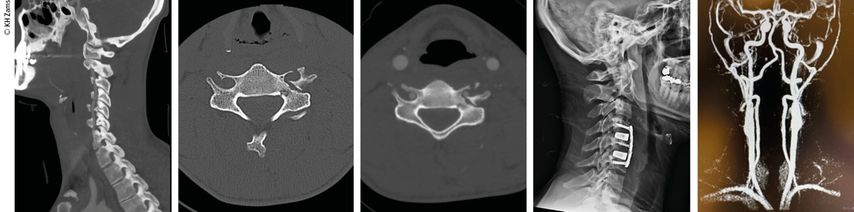

Abb. 4: Mann, 28a, Z.n. Schisturz; instabile Teardrop-Verletzung mit Dissektion A. vertebralis l.; Zervikobrachialgie mit Dysästhesie C6, mehrere kleine embolische Infarkte vertebrobasilär mit Koordinationsstörung; OP + Heparintherapie initial, anschließend APT